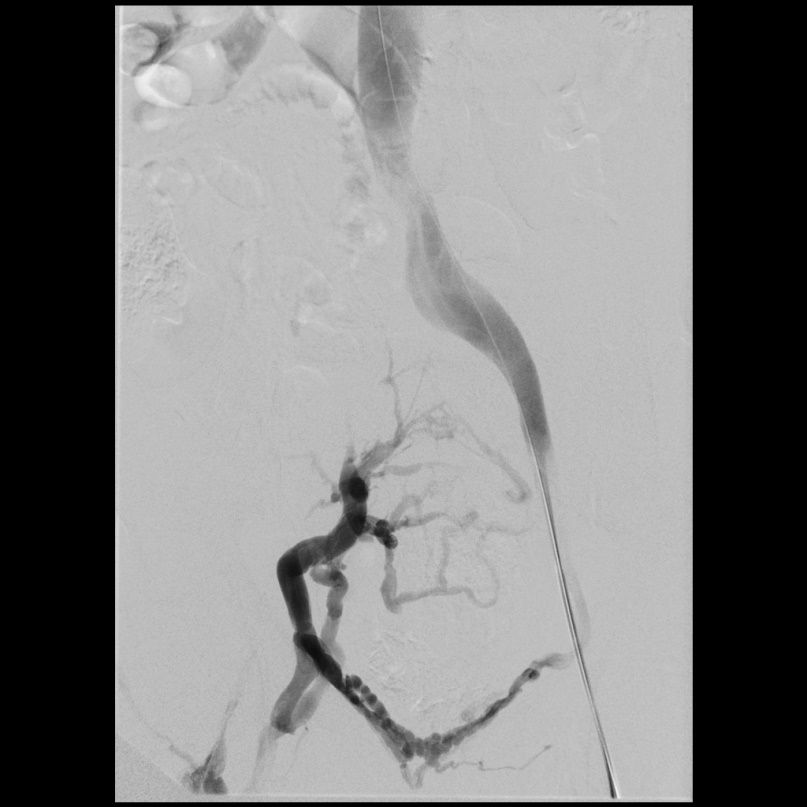

Beispiel eins Patienten mit Postthrombotischem Syndrom des rechten Beines (Schmerzen und Schwellung). Verschluss der Beckenvenen rechts (linkes Bild).